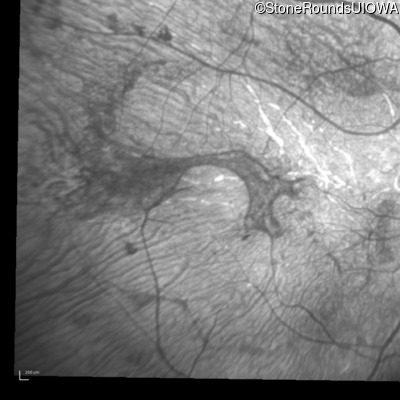

Infrared Fundus Photograph - Right - Light Perception

Exemplar